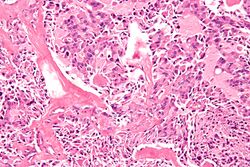

تكون الورم الصماوي المتعدد ( اختصاراً MEN ) هو حالة تشمل العديد من المتلازمات المتميزة التي تتميز بأورام الغدد الصماء، ولكل منها نمطها المميز. في بعض الحالات، تكون الأورام خبيثة، وفي حالات أخرى تكون حميدة. تحدث الأورام الحميدة أو الخبيثة للأنسجة غير الصماء كمكونات لبعض متلازمات الورم هذه.

تكون الورم الصماوي المتعدد من النوع 1 (MEN1) هو متلازمة سرطان الغدد الصماء الوراثية النادرة التي تتميز أساسًا بأورام الغدد الجار درقية (95٪ من الحالات)، والجهاز الهضمي والبنكرياس (GEP) (30-80٪ من الحالات)، والغدة النخامية الأمامية (15) - 90٪ من الحالات)).[7] كما تحدث أورام الغدد الصماء والأورام غير الصماء الأخرى بما في ذلك أورام قشر الكظر والغدة الدرقية، والأورام الشحمية الحشوية والجلدية، والأورام السحائية، والأورام الليفية الوعائية في الوجه والأورام الكولاجينية، وسرطان الغدة الصعترية والمعدة والشعب الهوائية. النمط الظاهري لـ MEN1 واسع، وقد تم وصف أكثر من 20 مجموعة مختلفة من مظاهر الغدد الصماء وغير الغدد الصماء. يجب الاشتباه في MEN1 في المرضى الذين يعانون من اعتلال الغدد الصماء في اثنين من الأعضاء الثلاثة المصابة المميزة، أو مع اعتلال الغدد الصماء في أحد هذه الأعضاء بالإضافة إلى قريب من الدرجة الأولى مصاب بمتلازمة MEN1.[citation needed]